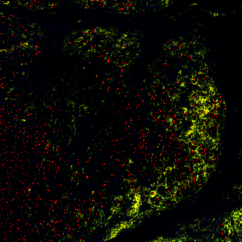

"The skin tumours we study develop resistance to targeted therapy in 75 to 80 percent of cases, which is quite alarming," says Lisa Haas, recent PhD graduate from the Obenauf Lab and first author of the study. "We found that acquired resistance to targeted therapy has a strong impact on the tumour’s immune cell composition, which could lead to resistance to immunotherapy."

The scientists found that tumours that had developed resistance to targeted therapy were short of a type of cells – dendritic cells – that are crucial to activate the immune system during immunotherapy. Not only were there fewer dendritic cells in these tumours, but they did not function properly. As a result, immunotherapy was ineffective in waking the immune system from slumber, and the tumours kept on growing, unnoticed.